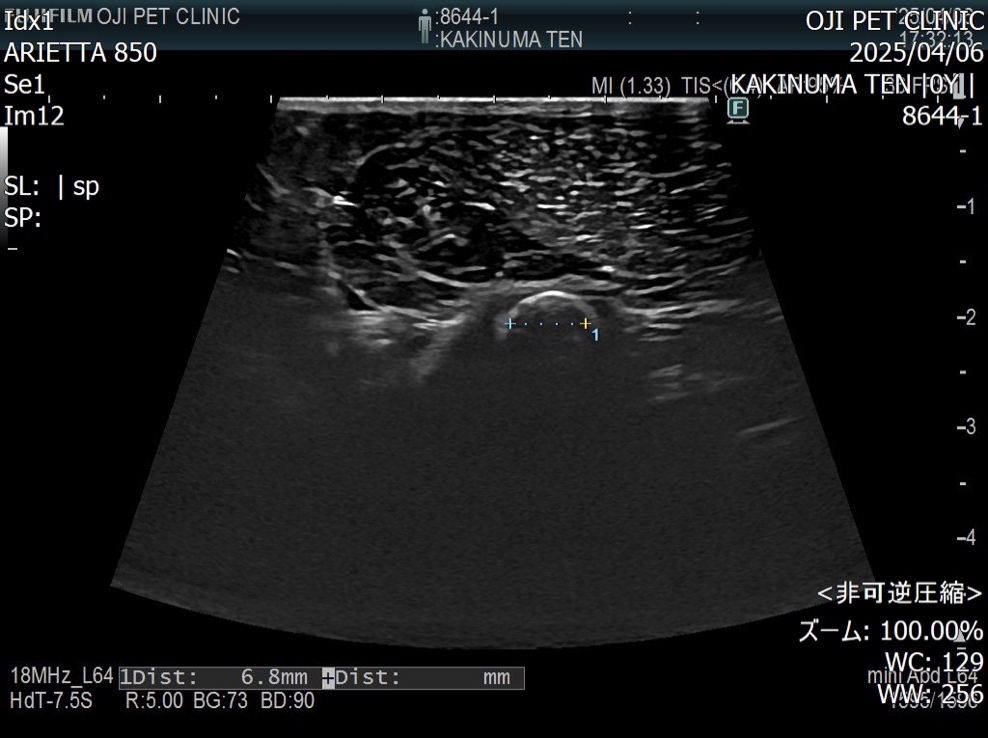

超音波検査にて膀胱内には結石が認められないことを確認

尿道内の石を確認しカテーテルで膀胱内に押し戻した様子